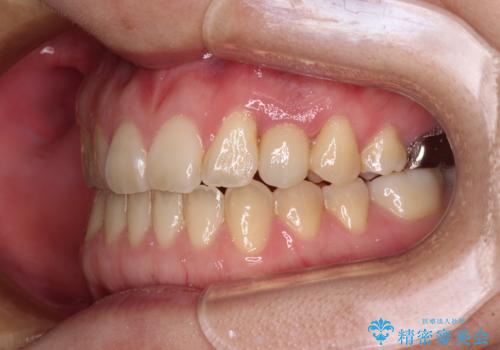

受け口で開咬を急速拡大装置とインビザラインで改善 欠損部分はインプラントにて補綴治療

矯正治療が終わるタイミングに合わせてインプラントの埋入を行っていたので、矯正治療を終了すると同時にセラミック補綴治療を行えました。

インビザラインの装着時間が不十分であったので、治療期間は長期間となりました。